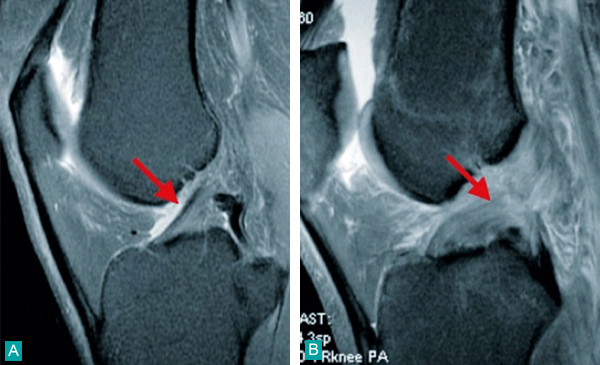

IRM coupe sagittale T2/FS. A : ligament croisé antérieur intact ; B : rupture du ligament croisé antérieur au fémur

Extrait de : Item 357 - Lésions péri-articulaires et ligamentaires du genou, de la cheville et de l'épaule